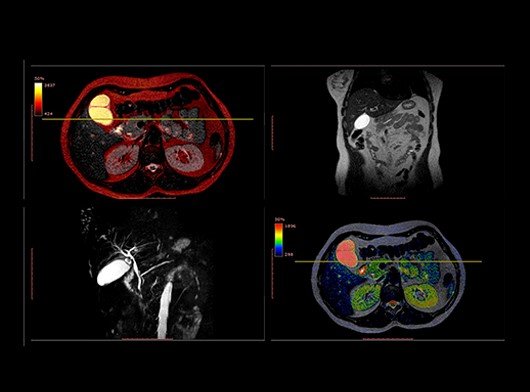

Магнитно-резонансная холангиопанкреатография (МРХПГ) – это вид магнитно-резонансной томографии (МРТ), который дает подробные изображения гепатобилиарной и панкреатической систем, включая печень, желчный пузырь, желчевыводящие протоки, поджелудочную железу и проток поджелудочной железы.